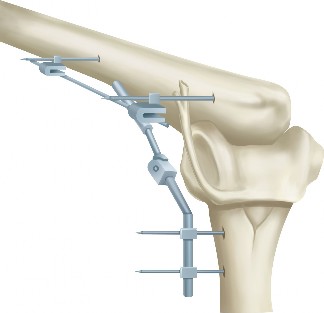

The patient undergoes resection arthroplasty with antibiotic cement spacer and a 6-week course of IV antibiotics. He returns to clinic 4 months later with improved pain, CRP <3, however, on examination he has a positive belly press sign and increased external rotation compared with the contralateral shoulder. Imaging is shown in Figure 2–57.

Figure 2–57

The correct answer is (D). The patient has completed his course of antibiotics and his spacer and is now an appropriate candidate for explanation of the cement spacer with revision shoulder arthroplasty, therefore Choices A and C are incorrect. The patient’s clinical examination findings point to rotator cuff tear (specifically subscapularis) which has occurred in the interval between his obtaining his initial total shoulder arthroplasty and his current examination. Therefore, total shoulder arthroplasty (Choice B) is contraindicated, and the patient should have a reverse total shoulder arthroplasty. Objectives: Did you learn...? Recognize the clinical presentation of a patient with infection after total shoulder arthroplasty?